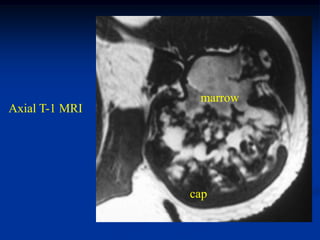

Case # 124.1                    AP and lat x-ray

50 year male with chondromyxoid fibroma proximal

tibia with 6 months of a tender tumor mass anterior tibia

Coronal T-1 MRI